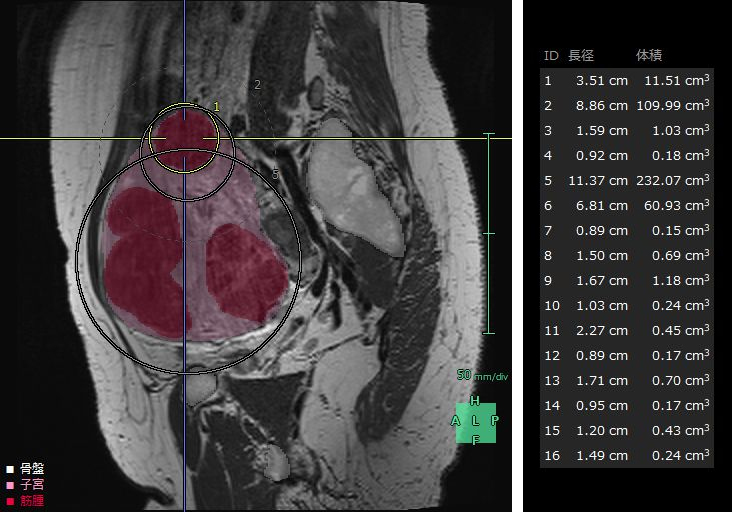

子宮筋腫は、成人女性の罹患率が20~30%と高頻度に見られる疾患*4で、機能温存が重要とされている。MRIや超音波画像診断装置の2D画像では筋腫や周囲組織の3次元的な把握が難しく、骨盤内の複雑な解剖構造の理解も困難である。また、筋腫の大きさや数、妊孕性温存の希望などにより様々な手技が適用されるが、筋腫の計測や手技の選択は各医師の経験則や感覚に基づいて行われているという課題がある。「婦人科臓器解析」ではMRIのT2画像からAI技術*2を活用した抽出エンジンを用いて子宮周囲の臓器をセグメンテーションし、ユーザーが子宮筋腫と判断した箇所の体積・数・深さの定量化を行うことができる。また、3Dで周辺組織との位置関係を把握することで筋腫手術の低侵襲化や取り残し防止等への寄与が期待される。